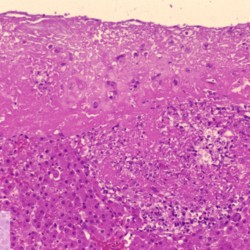

Etiquetes: N-854/00 1 total Feline Specie: Feline Organ: Liver Lesion: Hepatitis Lesion modifier: Hepatitis - Pyogranulomatous Disease: Feline infectious peritonitis Files/Expedient: N-854/00 Not viewed Títol Select...Avian (Exotic) (110)Avian (Poultry) (76)Bovine (317)Canine (935)Caprine (47)Equine (257)Feline (326)Ferret (19)General (127)Marine mammal (22)Non-human primate (20)Ovine (328)Porcine (379)Rabbit (61)Reptile (38)Rodent (28)Wildlife (91) Format Select...- (60)Abomasum (37)Adrenal gland (10)Blood (7)Blood vessel (50)Body as a whole (19)Bone (57)Bone marrow (21)Brain (93)Cloaca (1)Diaphragm (2)Ear (5)Esophagus (39)Eye (16)Fetus (12)Gallbladder (23)Gizzard (2)Heart (265)Intestine (356)Joint (32)Kidney (443)Larynx (5)Liver (326)Lung (264)Lymph node (91)Mammary gland (10)Mediastinum (1)Muscle (22)Nasal cavity (22)Nerve (7)Omasum (5)Oral cavity (63)Ovary (14)Oviduct (8)Pancreas (7)Parathyroid (5)Penis (10)Peritoneum (65)Pharynx (9)Pituitary gland (6)Placenta (7)Prostate (8)Proventriculus (3)Reticulum (1)Rumen (28)Sinus (7)Skin (181)Spinal cord (15)Spleen (105)Stomach (125)Teeth (1)Testicle (11)Thoracic cavity (31)Thymus (13)Thyroid gland (5)Tongue (32)Tonsils (11)Trachea (11)Urethra (5)Urinay bladder (61)Uterus (27)Vagina (1)Vulva (1)Yolk sac (1) Cobertura Select...- (152)Abomasitis (26)Abscess (27)Acidosis (1)Adenocarcinoma (20)Adenoma (9)Aerosacculitis (6)Agenesis (1)Agnathia (1)Alopecia (7)Amyloidosis (12)Aneurysm (6)Angiectasis (1)Anthracosis (1)Arteritis (11)Arthritis (15)Arthrogryposis (6)Artifact (4)Ascites (13)Atelectasis (8)Atherosclerosis (5)Atresia (1)Atrial septal defect (2)Atrophy (10)Autolysis (7)Bronchitis (6)Bronchopneumonia (26)Cachexia (2)Carcinoma (103)Cardiomyopathy (19)Cellulitis (2)Chemodectoma (4)Cholangiohepatitis (4)Cholangitis (19)Cholecystitis (4)Cholestasis (5)Chondrodysplasia (2)Chondrosarcoma (2)Chronic passive congestion (13)Chylothorax (2)Cirrhosis (6)Coelomitis (3)Coenurus cerebralis (4)Colitis (40)Congestion (17)Conjunctivitis (5)Coronitis (3)Cryptorchidism (3)Cyst (25)Cystitis (24)Dermatitis (69)Diaphragmatic hernia (4)Dilation (28)Discospondylitis (1)Disseminated intravascular coagulation (7)Dyschondroplasia (1)Dysplasia (29)Ectopia cordis (1)Ectopic ureter (1)Edema (55)Emphysema (5)Encephalitis (5)Endocardiosis (14)Endocarditis (26)Endometritis (5)Enteritis (118)Enterolith (6)Epulis (3)Esophagitis (14)Fasciitis (1)Fibrosis (7)Fibrous osteodystrophy (8)Fistula (1)Folliculitis (3)Fracture (2)Gastritis (34)Gingivitis (5)Glioma (8)Glomerulonephritis (21)Glossitis (25)Glycogenosis (1)Gout (8)Granuloma (2)Granulosa cell tumor (4)Hemangioma (9)Hemangiosarcoma (46)Hematoma (8)Hemoglobinuria (2)Hemopericardium (12)Hemoperitoneum (2)Hemorrhage (100)Hemosiderosis (7)Hemothorax (2)Hepatitis (78)Hernia (11)Histiocytosis (3)Hydatid cyst (11)Hydrocephalus (9)Hydrometra (1)Hydronephrosis (22)Hydropericardium (6)Hydrothorax (3)Hydroureter (5)Hyperkeratosis (8)Hyperostosis (4)Hyperplasia (37)Hypertrophy (9)Hypopigmentation (1)Hypoplasia (7)Hypopyon (1)Impaction (6)Infarction (63)Insulinoma (6)Intussusception (5)Jaundice (17)Laminitis (2)Laryngitis (2)Leiomyoma (5)Leukemia (13)Lipidosis (36)Lipoma (7)Lymphadenitis (45)Lymphadenopathy (7)Lymphangiectasia (6)Lymphangitis (5)Lymphoma (221)Malacia (11)Malignant melanoma (15)Mast cell tumor (11)Mastitis (8)Megaesophagus (2)Melanosis (3)Melena (4)Meningioma (6)Meningitis (6)Meningocele (2)Meningoencephalitis (5)Mesothelioma (5)Methemoglobinemia (2)Mineralization (10)Mucocele (5)Mucometra (1)Multilobular bone tumor (1)Mummification (3)Myelofibrosis (1)Myocarditis (4)Myositis (5)Necrosis (81)Nephritis (113)Nephroblastoma (6)Nephrosclerosis (1)Nephrosis (14)Neuritis (1)Obstruction (13)Omasitis (4)Omphalitis (1)Omphalophlebitis (7)Orchitis (4)Osteoarthrosis (5)Osteomyelitis (9)Otitis (2)Palatoschisis (3)Pancreatitis (3)Panniculitis (3)Papilloma (7)Parakeratosis (14)Patent ductus arteriosus (6)Peliosis hepatis (1)Perforation (17)Pericarditis (35)Peritonitis (39)Persistent right aortic arch (1)Pharyngitis (2)Pheochromocytoma (2)Phlebitis (2)Placentitis (6)Pleuritis (21)Pleuropneumonia (24)Pneumonia (109)Pneumothorax (3)Polycystosis (14)Polyp (5)Polyserositis (6)Posthitis (1)Proctitis (4)Prolapse (3)Prostatitis (3)Proventriculitis (1)Pyelonephritis (24)Pyometra (6)Pyothorax (4)Rhinitis (11)Rumenitis (6)Rupture (24)Salpingitis (3)Sarcoma (57)Sclerosis (1)Scoliosis (2)Seminoma (2)Sequestrum (2)Serous atrophy (14)Sinusitis (7)Splenitis (14)Splenomegaly (9)Spondylitis (6)Spondylosis (1)Stenosis (9)Stomatitis (32)Tenosynovitis (2)Teratoma (3)Thricobezoar (2)Thrombosis (16)Tonsilitis (4)Torsion (13)Tracheitis (4)Tympany (7)Typhlitis (8)Typhlocolitis (4)Ulcer (43)Urethritis (1)Urolithiasis (36)Uroperitoneum (1)Uveitis (1)Vasculitis (15)Ventricular septal defect (3)Volvulus (11) Matèria Select... - (14)- (1653)- (152)Abomasitis - Catarrhal (2)Abomasitis - Catarrhal-hemorrhagic (1)Abomasitis - Chronic (1)Abomasitis - Fibrinous-necrotizing (2)Abomasitis - Hyperplasic (5)Abomasitis - Hyperplasic - Chronic (1)Abomasitis - Necrotic (1)Abomasitis - Necrotizing (2)Abomasitis - Ulcerative (5)Adenocarcinoma (9)Aerosacculitis - Granulomatous (1)Amyloidosis - Chronic (1)Arteritis - Necrotic (2)Arteritis - Necrotizing (1)Arthritis - Chronic (4)Arthritis - Fibrinous-purulent (3)Arthritis - Serous (4)Arthritis - Subacute (1)Ascites - Serous (1)Atrophy - Serous (1)Bronchitis - Catarrhal (3)Bronchitis - Suppurative (1)Bronchopneumonia - Catarrhal-purulent (17)Bronchopneumonia - Fibrinous (1)Bronchopneumonia - Granulomatous (1)Bronchopneumonia - Purulent (1)Bronchopneumonia - Suppurative (5)Carcinoma - Adenocarcinoma (33)Carcinoma - Adenocarcinoma - Hepatocellular (2)Carcinoma - Adenocarcinoma - Mucinous (1)Carcinoma - Basosquamous (1)Carcinoma - Cholangiocellular (3)Carcinoma - Hepatocellular (4)Carcinoma - Metastatic (3)Carcinoma - Squamous cell carcinoma (13)Carcinoma - Transitional cell (2)Cardiomyopathy - Dilated (13)Cardiomyopathy - Hypertrophic (6)Cellulitis - Necrotizing (1)Cholangitis - Chronic (8)Cholangitis - Hyperplasic (3)Cholecystitis - Fibrinous-necrotizing (1)Coelomitis - Fibrinous (1)Coelomitis - Granulomatous (1)Colitis - Catarrhal (3)Colitis - Catarrhal-hemorrhagic (1)Colitis - Fibrinous (1)Colitis - Fibrinous-necrotizing (1)Colitis - Fibrinous-necrotizing (Diphtheritic) (6)Colitis - Granulomatous (2)Colitis - Hemorrhagic (4)Colitis - Hemorrhagic-necrotizing (3)Colitis - Necrotizing (2)Colitis - Ulcerative (6)Congestion - Chronic (2)Conjunctivitis - Hyperplasic (1)Conjunctivitis - Purulent (3)Coronitis - Ulcerative (1)Cystitis - Chronic (3)Cystitis - Fibrinous (1)Cystitis - Fibrinous-necrotizing (1)Cystitis - Follicular (1)Cystitis - Hemorrhagic (6)Cystitis - Hemorrhagic-ulcerative (1)Cystitis - Necrotizing (9)Cystitis - Perforated (1)Dermatitis - Granulomatous (14)Dermatitis - Hyperkeratotic (10)Dermatitis - Hyperplasic (proliferative) (1)Dermatitis - Hyperplastic (10)Dermatitis - Necrotizing (4)Dermatitis - Pustular (4)Dermatitis - Ulcerative (2)Dilation - Chronic (1)Discospondylitis - Necrotizing (1)Dysplasia - Follicular (5)Edema - Interstitial (6)Emphysema - Interstitial (1)Encephalitis - Granulomatous (1)Encephalitis - Nonsuppurative (1)Endocardiosis - Mitral (7)Endocardiosis - Mitral - Chronic (5)Endocarditis - Valvular (6)Endocarditis - Valvular - Mitral (7)Endocarditis - Valvular - Pulmonic (1)Endocarditis - Valvular - Subacute (1)Endocarditis - Valvular - Subaortic (5)Endocarditis - Valvular - Tricuspid (4)Endometritis - Purulent (3)Endometritis - Purulent-hemorrhagic (2)Enteritis - Catarrhal (23)Enteritis - Catarrhal - Acute (1)Enteritis - Catarrhal-hemorrhagic (5)Enteritis - Catarrhal-hemorrhagic - Acute (2)Enteritis - Fibrinous (16)Enteritis - Fibrinous - Acute (3)Enteritis - Fibrinous-necrotizing (7)Enteritis - Granulomatous (14)Enteritis - Granulomatous - Chronic (1)Enteritis - Granulomatous - Multifocal (1)Enteritis - Hemorrhagic (17)Enteritis - Hemorrhagic - Acute (1)Enteritis - Hemorrhagic-necrotizing (1)Enteritis - Hyperplasic (proliferative) (4)Enteritis - Necrotizing (4)Enteritis - Necrotizing - Acute (1)Enteritis - Necrotizing - Hemorrhagic (1)Enteritis - Necrotizing-ulcerative (2)Enteritis - Ulcerative (1)Enteritis - Ulcerative-hemorrhagic (1)Esophagitis - Erosive-ulcerative (6)Esophagitis - Necrotizing (4)Esophagitis - Ulcerative (1)Esophagitis - Ulcerative-necrotizing (1)Fasciitis - Fibrinous-purulent (1)Folliculitis - Purulent (2)Gastritis - Catarrhal (2)Gastritis - Chronic (1)Gastritis - Follicular (1)Gastritis - Hemorrhagic (2)Gastritis - Hemorrhagic-necrotizing (1)Gastritis - Hypertrophic (2)Gastritis - Inclusion bodies (1)Gastritis - Mineralization (1)Gastritis - Mycotic (1)Gastritis - Necrotizing (2)Gastritis - Ulcerative (6)Gastritis - Uremic (3)Gingivitis - Erosive (2)Gingivitis - Hyperplasic (proliferative) (1)Gingivitis - Necrotizing (1)Glomerulonephritis - Chronic (7)Glomerulonephritis - Membranoproliferative (3)Glomerulonephritis - Membranoproliferative - Chronic (1)Glomerulonephritis - Membranous (3)Glomerulonephritis - Membranous - Chronic (1)Glomerulonephritis - Proliferative (2)Glomerulonephritis - Subacute (1)Glossitis - Erosive (2)Glossitis - Granulomatous (6)Glossitis - Hyperplasic (1)Glossitis - Hyperplasic (proliferative) (2)Glossitis - Hyperplastic (1)Glossitis - Necrotizing (2)Glossitis - Necrotizing - Focal (1)Glossitis - Ulcerative (6)Glossitis - Ulcerative - Multifocal (1)Glossitis - Ulcerative - Subacute (1)Glycogenosis (1)Granuloma - Eosinophilic (1)Hemangiosarcoma - Metastatic (2)Hemorrhage - Acute (1)Hemorrhage - Subcapsular (3)Hepatitis - Abscess (9)Hepatitis - Acute (3)Hepatitis - Chronic (4)Hepatitis - Chronic interstitial (6)Hepatitis - Granulomatous (7)Hepatitis - Interstitial - Multifocal (1)Hepatitis - Interstitial - Subacute (1)Hepatitis - Necrotizing (17)Hepatitis - Necrotizing - Acute (2)Hepatitis - Necrotizing - Hemorrhagic (1)Hepatitis - Necrotizing - Subacute (1)Hepatitis - Pyogranulomatous (7)Hepatitis - Subacute (4)Hydronephrosis - Chronic (1)Hydropericardium - Chronic (1)Hyperplasia - Erythroid (1)Hyperplasia - Lymphoid (3)Hyperplasia - Myeloid (1)Hyperplasia - Nodular (8)Hypertrophy - Concentric (2)Hypertrophy - Eccentric (3)Infarction - Acute (17)Infarction - Acute - Multifocal (2)Infarction - Chronic (5)Infarction - Chronic - Multifocal (1)Infarction - Subacute (18)Infarction - Subacute - Focal (2)Laminitis - Chronic (2)Laryngitis - Necrotic (1)Laryngitis - Necrotizing (1)Leukemia - Lymphoid leukemia (2)Leukemia - Non-lymphoid leukemia (6)Lipidosis - Multifocal (1)Lipidosis - Panlobular (1)Lipidosis - Panlobular - Generalized (2)Lymphadenitis - Granulomatous (24)Lymphadenitis - Granulomatous - Chronic (3)Lymphadenitis - Hemorrhagic (1)Lymphadenitis - Necrotizing (5)Lymphadenitis - Necrotizing (caseous) (11)Lymphangitis - Granulomatous (1)Lymphangitis - Purulent (1)Lymphangitis - Ulcerative (1)Lymphoma - Alimentary lymphoma (7)Lymphoma - Cutaneous lymphoma (6)Lymphoma - Lymphosarcoma (2)Lymphoma - Mediastinal lymphoma (1)Lymphoma - Multicentric lymphoma (29)Malignant melanoma - Malignant (1)Malignant melanoma - Metastatic (1)Mast cell tumor - Metastatic (1)Mastitis - Fibrinous-purulent (2)Mastitis - Necrotic (1)Mastitis - Purulent (3)Mastitis - Suppurative (1)Meningitis - Fibrinous-purulent (2)Meningitis - Purulent (4)Meningoencephalitis - Necrotizing (3)Meningoencephalitis - Nonsuppurative (2)Mineralization - Metastatic (4)Myocarditis - Fibrous - Chronic (1)Myocarditis - Granulomatous (1)Myositis - Purulent (2)Necrosis - Acute (1)Necrosis - Cortical (5)Necrosis - Follicular (1)Necrosis - Papillary (8)Necrosis - Papillary - Acute (3)Necrosis - Subacute (3)Necrosis - Tubular (6)Nephritis - Embolic (2)Nephritis - Embolic suppurative (7)Nephritis - Granulomatous (27)Nephritis - Granulomatous - Chronic (1)Nephritis - Granulomatous - Multifocal (1)Nephritis - Interstitial (6)Nephritis - Interstitial - Acute (4)Nephritis - Interstitial - Chronic (41)Nephritis - Interstitial - Subacute (12)Nephritis - Purulent (7)Nephritis - Purulent - Acute (2)Nephritis - Purulent - Multifocal (3)Nephrosis - Cholemic (3)Nephrosis - Hemoglobinuric (10)Omasitis - Fibrinous-necrotizing (1)Omasitis - Hyperkeratotic (1)Omasitis - Necrotizing (2)Omphalophlebitis - Fibrinous-purulent (2)Omphalophlebitis - Purulent (3)Orchitis - Necrotizing (1)Osteomyelitis - Necrotizing (7)Osteomyelitis - Purulent (2)Otitis - Necrotizing (1)Otitis - Proliferative (1)Pancreatitis - Acute (1)Pancreatitis - Chronic (1)Pancreatitis - Granulomatous (1)Panniculitis - Fibrinous-purulent (1)Panniculitis - Necrotic (1)Panniculitis - Parasitic (1)Perforation - Acute (2)Pericarditis - Fibrinous (19)Pericarditis - Fibrinous - Subacute (1)Pericarditis - Fibrinous-necrotizing (1)Pericarditis - Fibrinous-purulent (3)Pericarditis - Fibrous (1)Pericarditis - Fibrous - Chronic (1)Pericarditis - Gangrenous (6)Pericarditis - Granulomatous (1)Pericarditis - Granulomatous - Chronic (2)Peritonitis - Acute (1)Peritonitis - Fibrinous (11)Peritonitis - Fibrinous - Subacute (1)Peritonitis - Fibrinous-purulent (5)Peritonitis - Fibrous (3)Peritonitis - Granulomatous (6)Peritonitis - Purulent (1)Peritonitis - Purulent-hemorrhagic (1)Peritonitis - Pyogranulomatous (3)Pharyngitis - Fibrinous-necrotizing (1)Pharyngitis - Ulcerative (1)Pheochromocytoma - Metastatic (1)Phlebitis - Purulent (1)Placentitis - Fibrinous-necrotizing (1)Placentitis - Necrotic (1)Placentitis - Necrotizing (1)Pleuritis - Chronic (1)Pleuritis - Fibrinous (3)Pleuritis - Fibrinous-purulent (2)Pleuritis - Fibrous (2)Pleuritis - Granulomatous (3)Pleuritis - Hyperplastic (2)Pleuritis - Purulent (2)Pleuritis - Pyogranulomatous (1)Pleuropneumonia - Fibrinous (13)Pleuropneumonia - Fibrinous-necrotizing (5)Pleuropneumonia - Granulomatous (2)Pleuropneumonia - Hemorrhagic-necrotizing (4)Pneumonia - Aspiration (11)Pneumonia - Bronchointerstitial (4)Pneumonia - Bronchointerstitial - Subacute (1)Pneumonia - Embolic (5)Pneumonia - Granulomatous (37)Pneumonia - Granulomatous - Multifocal (4)Pneumonia - Hemorrhagic-necrotizing (2)Pneumonia - Interstitial (7)Pneumonia - Interstitial - Acute (8)Pneumonia - Interstitial - Chronic (6)Pneumonia - Interstitial - Subacute (15)Pneumonia - Necrotizing (2)Pneumonia - Pyogranulomatous (2)Pneumonia - Verminous (5)Polyserositis - Fibrinous (6)Polyserositis - Fibrous (1)Proctitis - Fibrinous-necrotizing (1)Proctitis - Parasitic (2)Prostatitis - Purulent (1)Pyelonephritis - Acute (2)Pyelonephritis - Chronic (3)Rhinitis - Catarrhal (2)Rhinitis - Fibrinous (1)Rhinitis - Granulomatous (4)Rhinitis - Purulent (3)Rumenitis - Acute (1)Rumenitis - Erosive (1)Rumenitis - Necrotizing (1)Rupture - Acute (3)Sarcoma - Fibrosarcoma (12)Sarcoma - Hemangiosarcoma (11)Sarcoma - Histiocytic (7)Sarcoma - Metastatic (1)Sarcoma - Multilobular tumor of bone (1)Sequestrum - Chronic (2)Sinusitis - Suppurative (1)Splenitis - Granulomatous (8)Splenitis - Granulomatous - Chronic (1)Splenitis - Necrotizing (3)Splenitis - Necrotizing (caseous) (2)Spondylitis - Necrotizing (2)Stenosis - Intestinal (1)Stenosis - Valvular - Subaortic (4)Stomatitis - Erosive (12)Stomatitis - Erosive-ulcerative (3)Stomatitis - Fibrinous-necrotizing (1)Stomatitis - Fibrinous-necrotizing (Diphtheritic) (1)Stomatitis - Granulomatous (1)Stomatitis - Hyperplasic (1)Stomatitis - Hyperplasic (proliferative) (1)Stomatitis - Necrotizing (2)Stomatitis - Ulcerative (5)Stomatitis - Ulcerative - Multifocal (1)Stomatitis - Ulcerative-necrotizing (1)Tonsilitis - Necrotizing (4)Torsion - Acute passive hyperemia (5)Tracheitis - Catarrhal (3)Tracheitis - Fibrinous (1)Tracheitis - Granulomatous (1)Typhlitis - Catarrhal (1)Typhlitis - Fibrinous-necrotizing (2)Typhlitis - Hemorrhagic (2)Typhlitis - Ulcerative-hemorrhagic (1)Typhlocolitis - Fibrinous-necrotizing (2)Typhlocolitis - Proliferative (1)Ulcer - Chronic (6)Ulcer - Multifocal (2)Ulcer - Mycotic (1)Ulcer - Perforated (6)Urethritis - Hemorrhagic (1)Urolithiasis - Chronic (2)Uveitis - Granulomatous (1)Vasculitis - Granulomatous (1)Vasculitis - Necrotizing (1) Editor Select...- (1970)Acidosis (2)Actinobacillosis (Pleuropneumonia) (11)Aelurostrongylosis (2)African horse sickness (13)African swine fever (14)Alopecia X (1)Anaplasmosis (4)Anthrax (2)Aortic thromboembolism (feline) (7)Ascariasis (15)Aspergillosis (18)Atopic dermatitis (1)Atrophic rhinitis (3)Babesiosis (6)Blackhead (1)Bluetongue (11)Border disease (2)Bovine viral diarrhea (21)Brucellosis (2)Candidiasis (5)Canine distemper (14)Caprine arthritis-encephalitis (2)Capture myopathy (1)Cardiac insufficiency (17)Caseous lymphadenitis (7)Chlamydiosis (2)Classical swine fever (19)Clostridiosis (19)Coccidiosis (9)Coenurosis (4)Colibacillosis (21)Contagious ecthyma (7)Copper toxicosis (11)Cowdriosis (Heartwater) (3)Cryptococcosis (3)Cryptosporidiosis (2)Cysticercosis (23)Demodicosis (1)Diabetes (1)Dicrocoeliosis (5)Dictyocaulosis (4)Dirofilariasis (7)Discoid lupus erythematosus (3)Echinococcosis (17)Edema disease (7)Egg drop syndrome (1)Encephalitozoonosis (5)Enterotoxemia (1)Enzootic bovine leukosis (46)Epitheliogenesis imperfecta (3)Equine rhinopneumonitis (2)Equine verminous arteritis (strongylosis) (7)Erysipelas (5)Exudative epidermitis (7)Fasciolasis (11)Feline eosinophilic dermatoses (1)Feline hepatic lipidosis (8)Feline histiocytosis (4)Feline infectious peritonitis (38)Feline leukemia (4)Feline lower urinary tract disease (3)Feline panleukopenia (16)Feline viral rhinotracheitis (1)Flea allergy dermatitis (1)Foot and mouth disease (2)Gasterophilosis (4)Glasser's disease (15)Gousiekte (4)Gout (6)Haemonchosis (9)Hemolytic anemia (4)Hemorrhagic diathesis (1)Hepatic insufficiency (11)Hepatosis dietetica (7)Herpesvirosis (6)Hyperadrenocorticism (7)Hyperparathyroidism (10)Hypertrophic osteopathy (6)Hypervitaminosis D (1)Hypodermosis (1)Inclusion body hepatitis (4)Infectious bovine rhinotracheitis (5)Infectious bronchitis (5)Infectious canine hepatitis (13)Influenza (4)Juvenile nephropathy (8)Lamb dysentery (4)Leishmaniasis (28)Leptospirosis (1)Leukosis (5)Listeriosis (4)Lumpy skin disease (3)Maedi-visna (4)Malignant catarrhal fever (12)Mange (6)Mannheimiosis (5)Marek's disease (7)Metabolic bone disease (2)Mucoid enteropathy (5)Mulberry heart disease (5)Myasis (1)Mycobacteriosis (22)Mycosis fungoides (6)Myxomatosis (3)Necrobacillosis (5)Neonatal isoerythrolysis (6)Nocardiosis (4)Oestrosis (2)Onchocerciasis (1)Osteochondrosis (1)Ostertagiosis (6)Ovine pulmonary adenocarcinoma (5)Oxyuriasis (1)Pacheco's disease (4)Papillomatosis (6)Paratuberculosis (18)Parvovirosis (17)Pasteurellosis (11)Pemphigus foliaceus (1)Periodontal disease (1)Polioencephalomalacia of ruminants (4)Polyarteritis nodosa (3)Polycystic kidney disease (13)Porcine circovirosis (11)Porcine dermatitis and nephropathy syndrome (9)Porcine proliferative enteropathy (4)Porcine reproductive and respiratory syndrome (6)Porcine stress syndrome (1)Pox (13)Pregnancy toxemia (3)Proventricular dilatation disease (2)Pseudotuberculosis (yersiniosis) (2)Psittacine beak and feather disease (PBFD) (5)Pyoderma (4)Q fever (4)Rabbit hemorrhagic disease (2)Renal insufficiency (12)Reticuloendotheliosis (2)Rhodococcosis (1)Rickets (1)Rinderpest (2)Salmonellosis (34)Sarcosporidiosis (2)Schmallenberg (7)Septicemia (23)Spirocercosis (11)Streptococcosis (5)Strongylosis (1)Swine dysentery (5)Systemic coronavirosis (5)Tetralogy of Fallot (5)Theileriosis (13)Thromboembolism (5)Toxoplasmosis (11)Transmissible viral proventriculitis (1)Traumatic reticuloperitonitis (3)Traumatism (16)Tuberculosis (58)Ulcerative lymphangitis (1)Uremic syndrome (20)Viral arthritis (6)White muscle disease (9)Wobbler syndrome (2)Xanthomatosis (1)Zygomycosis (4) Idioma Select...- (1180)Bacterial (501)Degeneration (106)Fungal (46)Hemodynamic (112)Idiopathic (22)Inflammation (58)Malformation (88)Neoplasia (343)Nutritional (41)Parasitic (243)Physical/Chemical (93)Toxic (44)Viral (304) Ítem destacat Porcine Sow. Porcine Ulcerative Dermatitis Syndrome (PUDS). Interface dermatitis. Lesions were neither painful nor pruritic. University of Pretoria, South…